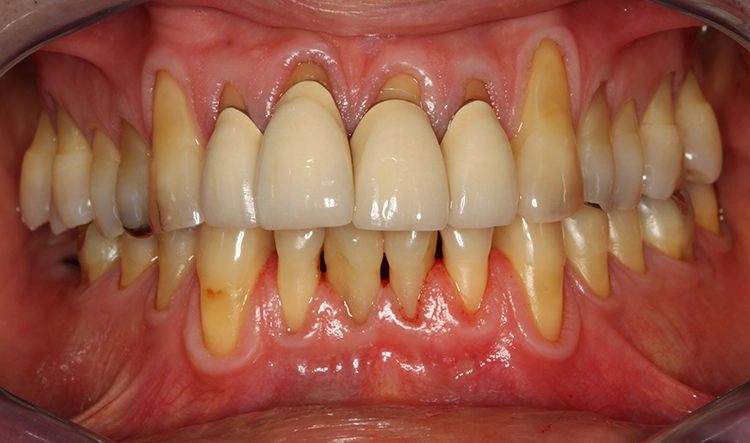

Egger/Wermuth/GrevenRote Ästhetik: Im Ober- und Unterkiefer zeigten sich generalisiert ausgedehnte Rezessionen mit bis zu 8 mm Attachmentverlust vor allem im Bereich der Eckzähne (Miller-Klasse III; Rezessionstyp [RT] 2 [69]. Das Band an keratinisierter Schleimhaut ist durchgehend vorhanden. Die Breite variiert im Eckzahnbereich von 1 mm bis zu 2 mm im Bereich der Unterkieferfrontzähne, der Prämolaren und Molaren (Abb. 1). Die fazialen Rezessionen sind mit approximalem röntgenologischem Attachmentverlust im koronalen Wurzeldrittel (Abb. 2) und Papillenverlust im Bereich zwischen den Kontaktpunkten und der approximalen Schmelz-Zement-Grenze assoziiert (Abb. 1). Der Patient verfügt über eine schmal geformte Oberlippe. Die Lachlinie verläuft mittelhoch (Abb. 3).

Dentalstatus: Es zeigen sich generelle Abrasionen, Attritionen und Erosionen im Ober- und Unterkiefer. Die ursprüngliche anatomische Kauflächenstruktur in den Seitenzahnbereichen ist durch die massiven erosions- und attritionsbedingten Zahnhartsubstanzverluste nicht mehr vorhanden (Tab. 2). Aufgrund der massiven Zahnschmelzverluste erscheint die Zahnfarbe insgesamt gelblicher. Der Patient wünscht sich im Rahmen der Rehabilitation in dieser Frage eine merkliche Verbesserung.

Parodontale Gesundheit bei Attachmentverlust, Bruxismus, Erosion. Abbildung 1 sowie 6 bis 9 zeigen den Anfangsbefund als intraoralen Fotostatus.*